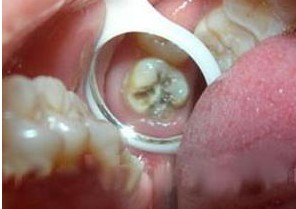

補(bǔ)牙齒多少錢?漳州附屬口腔醫(yī)院專家介紹說,補(bǔ)牙齒多少錢與牙齒損壞的程度和補(bǔ)牙材料有關(guān)。齒損壞的程度一般按牙洞的大小來定義,一般醫(yī)生會(huì)根據(jù)牙洞的大小來定補(bǔ)牙的價(jià)格,牙洞越大,費(fèi)用就越多。

補(bǔ)牙齒多少錢,從以上的介紹可知,補(bǔ)牙的費(fèi)用不僅與材料有關(guān),而且與牙洞的大小程度有關(guān),牙科專家提醒:如果你發(fā)現(xiàn)自己有了牙洞,一定要盡早治療,如果牙齒壞到了一定程度,就不是單純的補(bǔ)牙就可以了,需要根管治療,這時(shí)補(bǔ)牙的費(fèi)用就有可能翻倍。